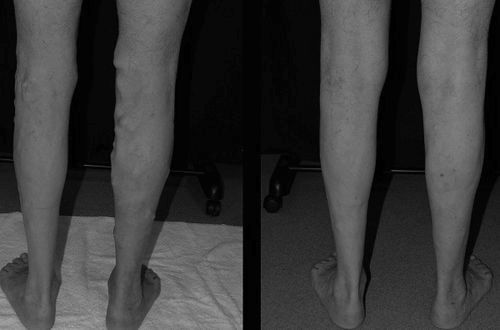

Вплив відбувається незалежно від калібру хворий вени. Це може бути дрібна судинна сіточка, або велике вузлове утворення. Вже на наступний день хворий може повністю повернутися до свого звичного способу життя, з незначними обмеженнями.

На даний момент існує досить багато способів радикального позбавлення від варикозної хвороби. Це і склеротерапія, флебектомія, радіочастотне вплив. Видалення варикозу лазером проводиться в тому випадку, якщо:

- відбулося розширення вен до 10 мм,